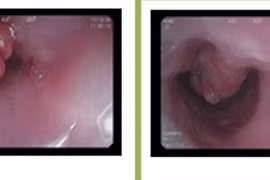

Những triệu chứng u thực quản thường diễn biến âm thầm, không rầm rộ, khiến nhiều người chủ quan và chỉ đi khám khi bệnh đã ở giai đoạn muộn.

So với mổ mở kinh điển, nội soi cắt u thực quản ít xâm lấn, có thể lấy triệt để u và vét hạch hiệu quả đặc biệt với bệnh nhân ung thư giai đoạn sớm.